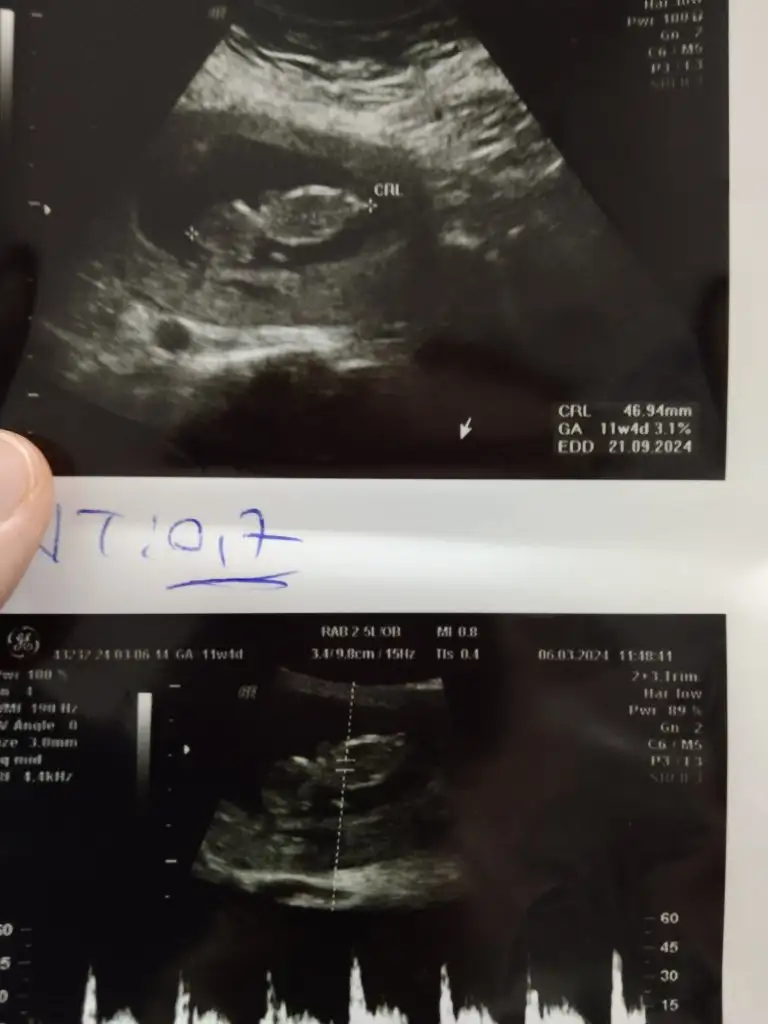

Kızlar bana da cinsiyet tahmini yapar misiniz iki doktora gittim bu hafta ama hiç tahmin bile yapmadılar. 13 haftalık olduk bugün.

• IMG_20240306_131429.webp

IMG_20240306_131429.webp

20,9 KB · Görüntüleme: 91

Kızlar nub teorisi anlayan varsa yorum alabilir miyim ben erkek diyorum bakalım siz ne diyecek siniz